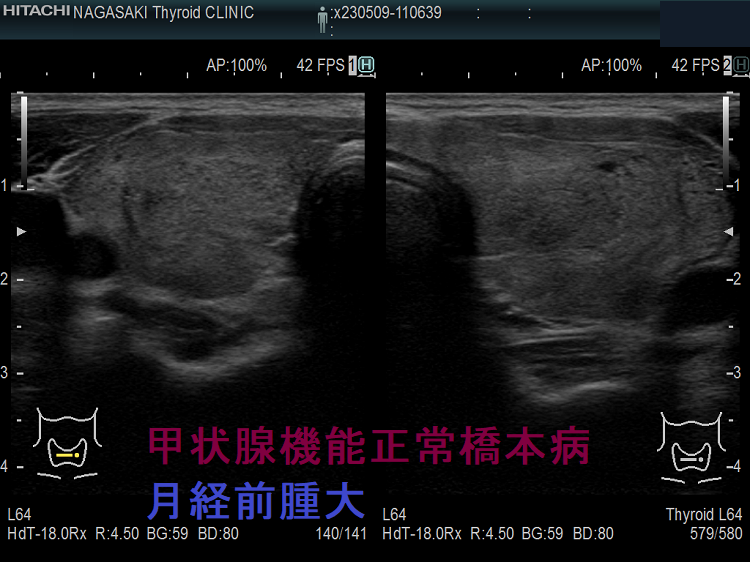

生理前の腫大した甲状腺 単純性甲状腺腫(Simple Goiter) 超音波(エコー)画像。特に、喉(のど)の違和感はありません